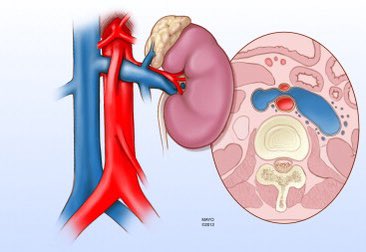

Nutcracker syndrome is the compression of the left renal vein by the superior mesenteric artery. It can mimic other urologic disease, as it’s symptoms are often nonspecific including flank pain, hematuria, pelvic congestion, or varicocele.

Nutcracker syndrome is the compression of the left renal vein by the superior mesenteric artery.

It can mimic other urologic disease, as it’s symptoms are often nonspecific including flank pain, hematuria, pelvic congestion, or varicocele.